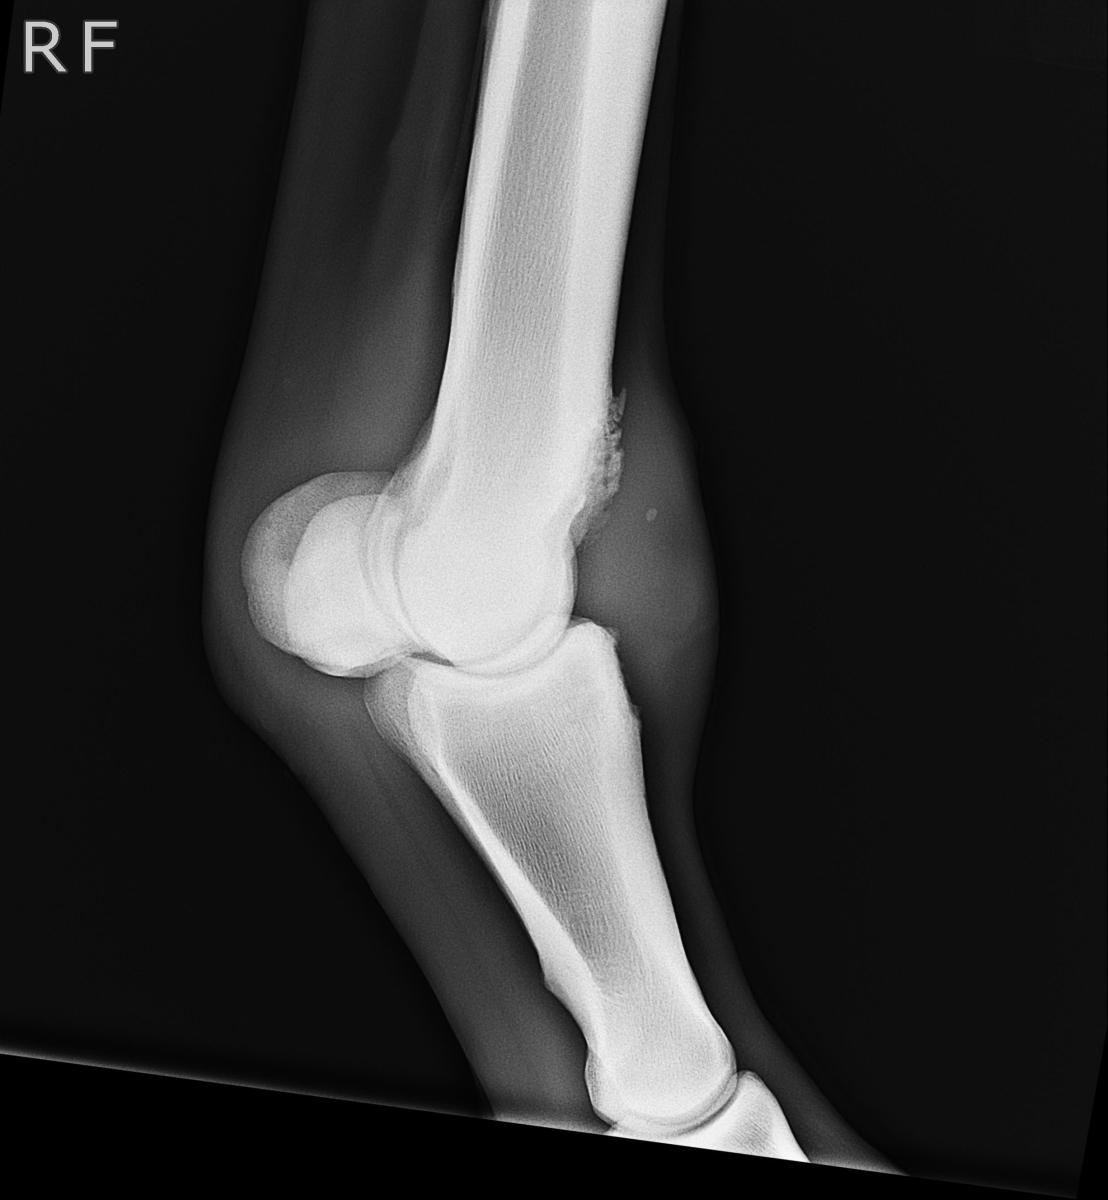

アユ号は笠松競馬、1月8日勝利後右前脚球節全面に骨膜炎が出ました。

X-Pも参考にしてください。